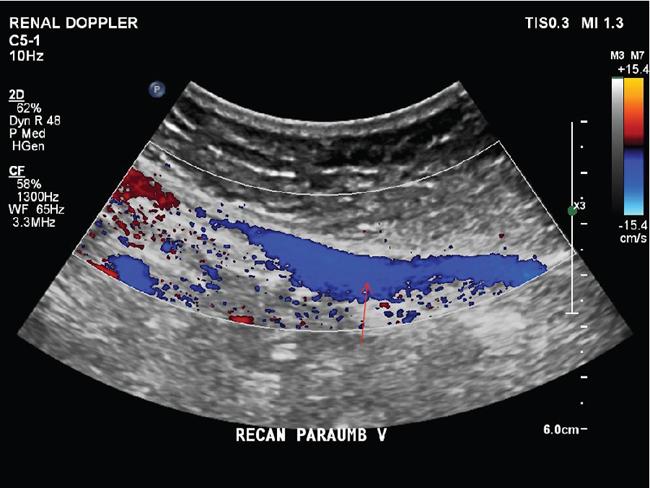

Shrinivas B. Desai, Ritu K. Kashikar, Aman Snehil, Ajay Jhaveri Cirrhosis is a late stage of irreversible scarring of the liver causing abnormality in liver structure and function. Multiple conditions and factors can cause repeated liver damage and scarring ultimately leading to cirrhosis. The most feared complication of liver cirrhosis is the development of hepatocellular carcinoma (HCC). Portal hypertension (PHT) is seen with a variety of conditions but cirrhosis happens to the most important cause. Imaging plays a vital role in noninvasive diagnosis and treatment planning of both cirrhosis and PHT. Liver imaging reporting and data system (LI-RADS) is a standardized reporting system assigning an observation risk of representing HCC. This chapter focuses on discussing aetiologies and imaging of PHT with a lucid review of L1-RADS 2018 version. The portal blood circulation is a unique circulatory circuit as it connects two capillary beds between the liver parenchyma at one end and the gastrointestinal tract and splenic parenchyma at the other end. The portal system ramifies in the liver and ultimately ends in the hepatic sinusoids from where the blood ultimately drains into the inferior vena cava (IVC). The portal vein (PV) originates from the capillary beds in the stomach, intestine and the spleen. The main PV is formed behind the neck of the pancreas by the confluence of the superior mesenteric vein (SMV) and splenic vein. It continues to the porta hepatis where it bifurcates into the left and right branches as it carries nutrient rich but oxygen poor blood to the liver (Fig. 9.9.1). The PV makes up for 75%–80% of the liver’s blood supply while the hepatic artery which arises from the celiac trunk makes up for the remaining 25%. A pathological increase in the portal venous pressure is referred to as PHT. PHT is most often a sequel of chronic parenchymal liver disease and leads to major life-threatening complications due to bleeding from the collateral circulation (most commonly oesophageal varices). Direct measurement of portal pressure (PP) is invasive and often not feasible in most patients and thus imaging plays an important role in the diagnosis of PHT and its complications. The normal portal venous pressure ranges between 5 and 10 mmHg, which is the equivalent of 7–14 cm H2O. The normal hepatic venous pressure gradient (HVPG) is the pressure gradient between the PV and the IVC, is typically 1–5 mmHg. Presence of PHT is indicated by a wedged hepatic venous pressure of more than 5 mmHg. Other definitions include a splenic pressure of more than 15 mmHg or an intraoperative PP of greater than 30 cm H2O. The complications of PHT are seen when HVPG is greater than 10 mmHg and hence this value defines clinically significant PHT. Variceal bleeding is seen with a pressure greater than 12 mmHg. In ideal conditions, the portal circuit is a high flow, low resistance circuit as it has to allow substantial flow rates of 700–1000 mL/min to the hepatic parenchyma from the gastrointestinal tract. Anatomical changes in the organization of the hepatic lobule can result in rise in the portal resistance. These can occur in the form of collagen deposition in the space of Disse, fibrotic scars formed due to regenerative nodule (RN) formation, loss of normal elasticity of the endothelium and distal venous thrombosis. Changes in splanchnic haemodynamics due to factors that increase splanchnic blood flow and increase in intrahepatic vascular resistance due to transformation of stellate cells into myofibroblasts also contribute to the increase in PP gradient. In Western countries, alcoholic cirrhosis and viral cirrhosis are the leading causes of PHT and oesophageal varices. The viral causes form majority of cases leading to cirrhosis and PHT in the Far East and Middle Eastern countries while Schistosomiasis remains an important cause in the African countries. Worldwide, nonalcoholic steatohepatitis (NASH) and hepatitis C are the emerging causes of chronic liver disease (CLD) and PHT. PHT can be classified as cirrhotic and noncirrhotic depending on whether it is associated with cirrhosis or not. This distinction is important as noncirrhotic causes like PV thrombosis are at high risk of development of bleeding but tend to have a better chance of surviving a variceal bleed than a patient with decompensated alcoholic cirrhosis due to preserved hepatic synthetic functions in the former. PHT can also be classified on the basis of the location of the pathology into prehepatic, hepatic and posthepatic causes. Hepatic causes can further be divided into presinusoidal, sinusoidal and postsinusoidal. The causes of portal hypertension have been denoted in Table 9.9.1. The direct measurement of the PP by measuring the HVPG is invasive, expensive not readily available in all patients. Thus, imaging plays an important role in the diagnosis of PHT. Various modalities are used for the imaging diagnosis of PHT. Ultrasonography (USG) and Doppler evaluation have the advantage of being inexpensive, readily available and bedside modality (Table 9.9.2). The role of ultrasound and Doppler in imaging of PHT is to: Grey scale imaging is useful in evaluating the splenoportal anatomy. The evaluation should begin with the liver morphology. Signs of cirrhosis like nodularity of the liver surface with relative atrophy of the right lobe and prominence of the left lobe and caudate should be looked for. Hepatic echotexture appears coarse and more echogenic (Table 9.9.3). Increase in portal venous diameter is a sign of PHT (Fig. 9.9.2). Portal venous diameter of more than 13 or 15 mm has low sensitivity for diagnosing PHT of only 40%–12.5%, respectively. Absolute measurement of the portal diameter as a sign of PHT is also fallacious as in presence of collateral circulation or hepatofugal flow; there may actually be a decrease in the PV diameter. Therefore, a more accurate sign is respiratory variation of PV diameter. An increase in PV diameter of less than 20% with deep inspiration has been reported to indicate PHT with a sensitivity of 80% and specificity of 100%. This has been reported to be an accurate indicator of cirrhosis. Hepatic vein straightness, uniformity of vein wall echogenicity and visualization of at least 1 cm segment of the hepatic vein are the parameters used for evaluation. Splenomegaly is defined as bipolar splenic diameter of greater than 12 cm or largest splenic cross-sectional area passing through the hilum of greater than 45 cm2, and occurs secondary to PHT (Fig. 9.9.3). A total of 65%–80% patients with cirrhosis have splenomegaly on ultrasound. Patients with cirrhosis due to viral hepatitis and primary biliary cirrhosis show splenomegaly more frequently than those with alcoholic cirrhosis. This is an accurate sign of PHT. USG is extremely sensitive with respect to detecting subclinical ascites. Perihepatic space is the most usual site of visualization of minimal ascites. In normal subjects, this ratio is approximately 0.07 and a value above 0.1 suggests the diagnosis of PHT with a 95% sensitivity and specificity. The normal spectral waveform of the hepatic artery is a low resistance flow pattern with forward flow in diastole and a resistivity index in the range of 0.5–0.7. In PHT, the resistivity index of the hepatic artery increases with high resistance flow pattern due to increased peripheral vascular resistance. Resistance index (RI) > 0.78 in the intrahepatic branches of the hepatic artery has been reported to have a sensitivity of 50% and a specificity of 100% for the detection of PHT (Fig. 9.9.11). Pulsatility index (PI) > 1.05 suggests severe PHT with a sensitivity of 86% and specificity of 88% (Fig. 9.9.11). Patency of hepatic veins should be evaluated to rule out Budd–Chiari syndrome as a cause of PHT. The normal hepatic venous waveform (HVW) reflects right atrial activity and this results in a triphasic waveform with one positive and two negative waves. In PHT, this waveform becomes monophasic or biphasic. A monophasic HVW has a sensitivity and specificity of 74% and 95%, respectively, in the diagnosis of severe PHT (Fig. 9.9.12). Dilatation of the splanchnic veins – the SMV and the splenic vein – more than 11 mm are suggestive of PHT with a sensitivity and specificity of 72% and 100%, respectively. A reduction in the respiratory variation of the splenic vein and SMV to less than 40% had a sensitivity and specificity of 79.7% and 100%, respectively, for the diagnosis of PHT (Fig. 9.9.13). The splenic artery reveals an increase in the resistivity index and an RI of >0.63 and a PI of >1 have a sensitivity and specificity of 84.6% and 70.4% for the diagnosis of PHT. Presence of portosystemic collaterals like patent paraumbilical vein, dilated left gastric and short gastric veins are 100% specific sign for PHT (Figs. 9.9.14–9.9.16). Recanalization of the paraumbilical vein, known as the Cruveilhier–Baumgarten syndrome is observed in 43% of patients with PHT, and this is the easiest collateral to assess during the US examination. Various portosystemic collaterals that occur in PHT have been discussed in details in subsection on CT findings in PHT. No Doppler parameter is considered reliable enough to measure PP with sufficient accuracy for use in clinical practice. Oesophageal varices are often present in patients with portosystemic collaterals. Appearance or increase in number of collaterals along with splenomegaly has a high association with variceal formation and growth. USG helps in diagnosis of prehepatic causes like portal stenosis or thrombosis by demonstrating the patency and morphology of the splenoportal system. Arteriovenous fistulae and tumours causing vascular thrombosis as aetiology can be readily detected. USG helps in diagnosis of features of cirrhosis and thus helps differentiate noncirrhotic causes of PHT. USG allows diagnosis of fatty liver disease, which is an emerging cause of cirrhosis. Among the posthepatic causes, USG aids in establishing the diagnosis of Budd–Chiari syndrome by demonstrating the patency and morphology of the IVC and hepatic veins. Owing to the inability of CT to detect flow direction, portal flow rates or pressure gradients, CT is not the primary modality in diagnosis of PHT. Similar to USG dilatation of portosystemic system is a feature of PHT (Fig. 9.9.17). Changes in cirrhosis if present can be seen in the form of surface nodularity, nodules and fibrous septae. CT plays an important role in diagnosis of portal venous thrombosis and evaluating its extent. An acute thrombus is seen as a hypodense filling defect in the vessel causing distension of the venous lumen. Surrounding fat stranding can be seen. A chronic thrombus appears as an eccentric filling defect usually along the wall and is often associated with decrease in vessel diameter. Calcification may be seen in chronic thrombi. Multidetector computed tomography (MDCT) is a useful tool to evaluate portosystemic collateral circulation and recognize complications of PHT. 3D angiography can help understand portal venous and complex variceal anatomy and plan treatment. The various portosystemic collaterals are discussed below. They can be classified into those draining into superior vena cava (SVC) and those draining into the IVC. Magnetic resonance imaging (MRI) is a noninvasive modality used in the evaluation of PHT without the use of ionising radiation. It provides evaluation of parenchymal abnormalities, collaterals and characterization of tumours (Fig. 9.9.28). Spin echo sequences allow characterization of liver masses and liver parenchyma. Loss of flow void allows for detection of thrombosis. Time-of-flight (TOF) angiography is useful in assessing the portal venous system and allows for successful detection of PV thrombosis. The disadvantages of TOF are motion artefacts caused by breathing, long acquisition times and incomplete coverage of the portal venous system. Novel imaging techniques include phase contrast, T1 mapping and magnetic resonance elastography (MRE). The advantage of phase contrast over TOF imaging is that phase contrast imaging acquires information regarding the flow direction in addition to the information regarding the flow velocity. On-phase contrast images signal within vessel is hyperintense when flow is cranial and hypointense when flow is caudal. Look-Locker imaging technique using gradient echo (GRE) MRI sequences with inversion recovery pulse is used to quantify fibrosis by measuring precontrast T1 relaxation times. Interventions in PHT can be aimed at diagnosis or more commonly at management of complications of PHT. HVPG measurement, which is the gold standard for the diagnosis of PHT, can be achieved through cannulation of the PV. Transjugular hepatic biopsy is another diagnostic invasive technique that also allows indirect measurement of PP. Disadvantages include deterioration of hepatic function caused by diversion of portal venous blood flow and shunt dysfunction. TIPSS is contraindicated in patients with congestive heart failure, severe pulmonary hypertension, severe tricuspid regurgitation and hepatic failure. In this technique, a catheter is advanced from the femoral vein into the outlet of the gastrorenal, usually in the region of the left renal vein. The shunt is then occluded with a balloon and sclerosant is injected retrograde to occlude the gastric varices. Histological development of RNs surrounded by fibrous septae in response to chronic liver injury, progressing PHT and end-stage liver disease is termed as cirrhosis. Although initially considered an end-stage phenomenon in CLD, recent evidence suggests that the histological fibrosis can be reversible in early stages with the initiation of specific therapies, for example, in viral cirrhosis with the initiation of antiviral therapy. The one-year mortality rate in cirrhosis varies widely from 1% to 57% depending on the occurrence of complications. Cirrhosis can have a wide variety of causes ranging from congenital to acquired and infectious to noninfectious. It is also a major aetiologic risk factor for the development of HCC. Imaging plays an important role in aetiologic diagnosis of this diverse entity as well as in the diagnosis and management of its complication and surveillance for oncological transformation.

F. Portosystemic collateral channels (Table 9.9.5)